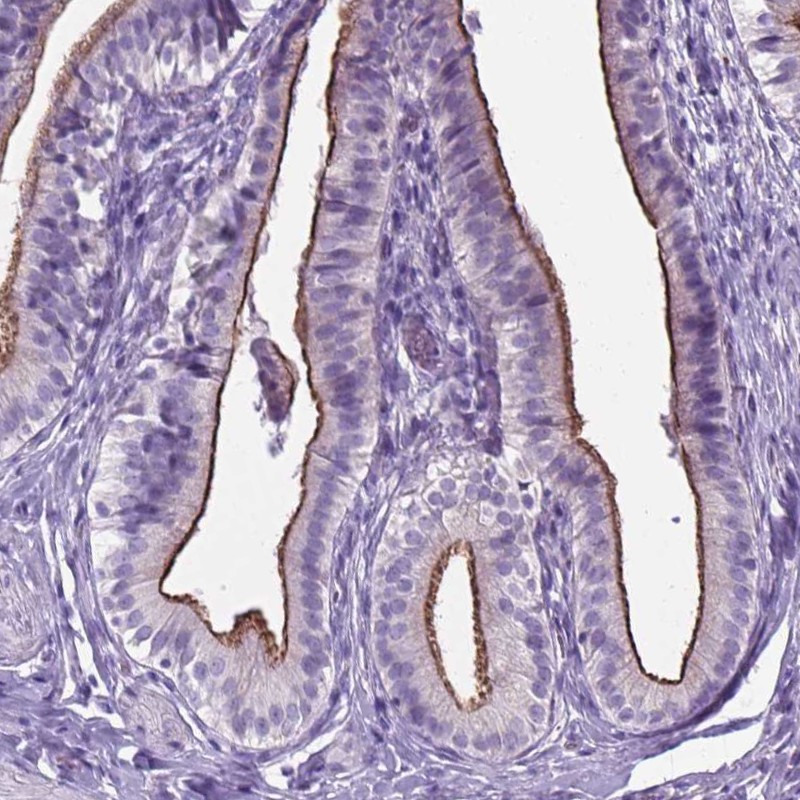

Immunohistochemical staining of human gallbladder shows strong apical membranous positivity glandular cells.